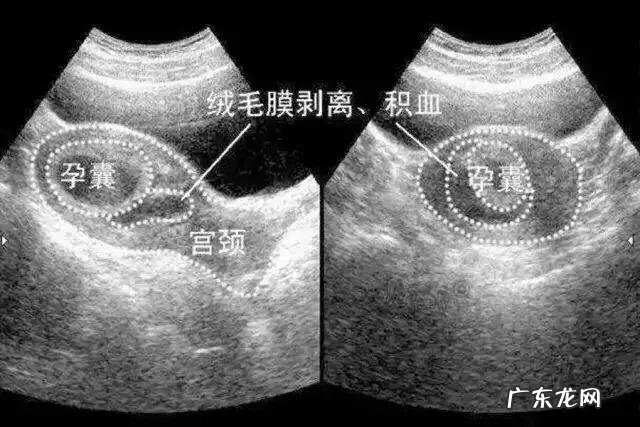

医生会经常感慨时代的进步 , 现在疾病也与时俱进了 , 很多孕妈可能不知什么是绒毛 , 绒毛是胎盘的主要组织 , 因为是纤细的 , 柔软的组织 , 孕早期像一朵绒花 , 所以称为绒毛 , 绒毛的底部有一层膜 , 叫绒毛膜 , 胎盘早期 , 绒毛均匀分布于整个绒毛膜表面 。绒毛的发育使其与子宫的接触面增大 , 并且与子宫壁越粘越紧 , 有利于胚胎与母体间的氧气及物质交接 , 因为绒毛的营养丰富 , 血供充足而枝干茂盛 , 有时血流循环受阻 , 或绒毛发育不良 , 还有一些不明原因 , 就会发生绒毛膜下血肿 , 一般情况下 , 孕妈可能都不会有明显的感觉 , 也有一些孕妈会出现阴道流暗红色或深褐色的血 , 量不多 , 无腹痛 , 去医院B超检查 , 医生可能就会看到绒毛膜下有血肿了 , 这个时候 , 胎儿一般都无恙 , 因为胎儿是生长在羊膜腔内 , 而绒毛是在羊膜腔外围 , 羊膜腔是封闭的 , 羊膜和绒毛之间隔着好几层膜 , 所以绒毛膜下血肿刚开始发生影响不了宝宝 。

B超报告单上可能会写上这样的字样:低回声或无回声的液性暗区包绕着部分妊娠囊 , 表面不规则 , 呈月牙形、三角形或环形 , 这种字样的报告就是提示我们这个孕妈有绒毛膜下血肿或绒毛膜下出血了 。我们医生看到B超单 , 首先关注绒毛膜下出血的程度 , 小于孕囊周边的1/3为轻度 。达到孕囊周边的1/3—1/2为中度 , 大于孕囊周边的1/2为重度 。